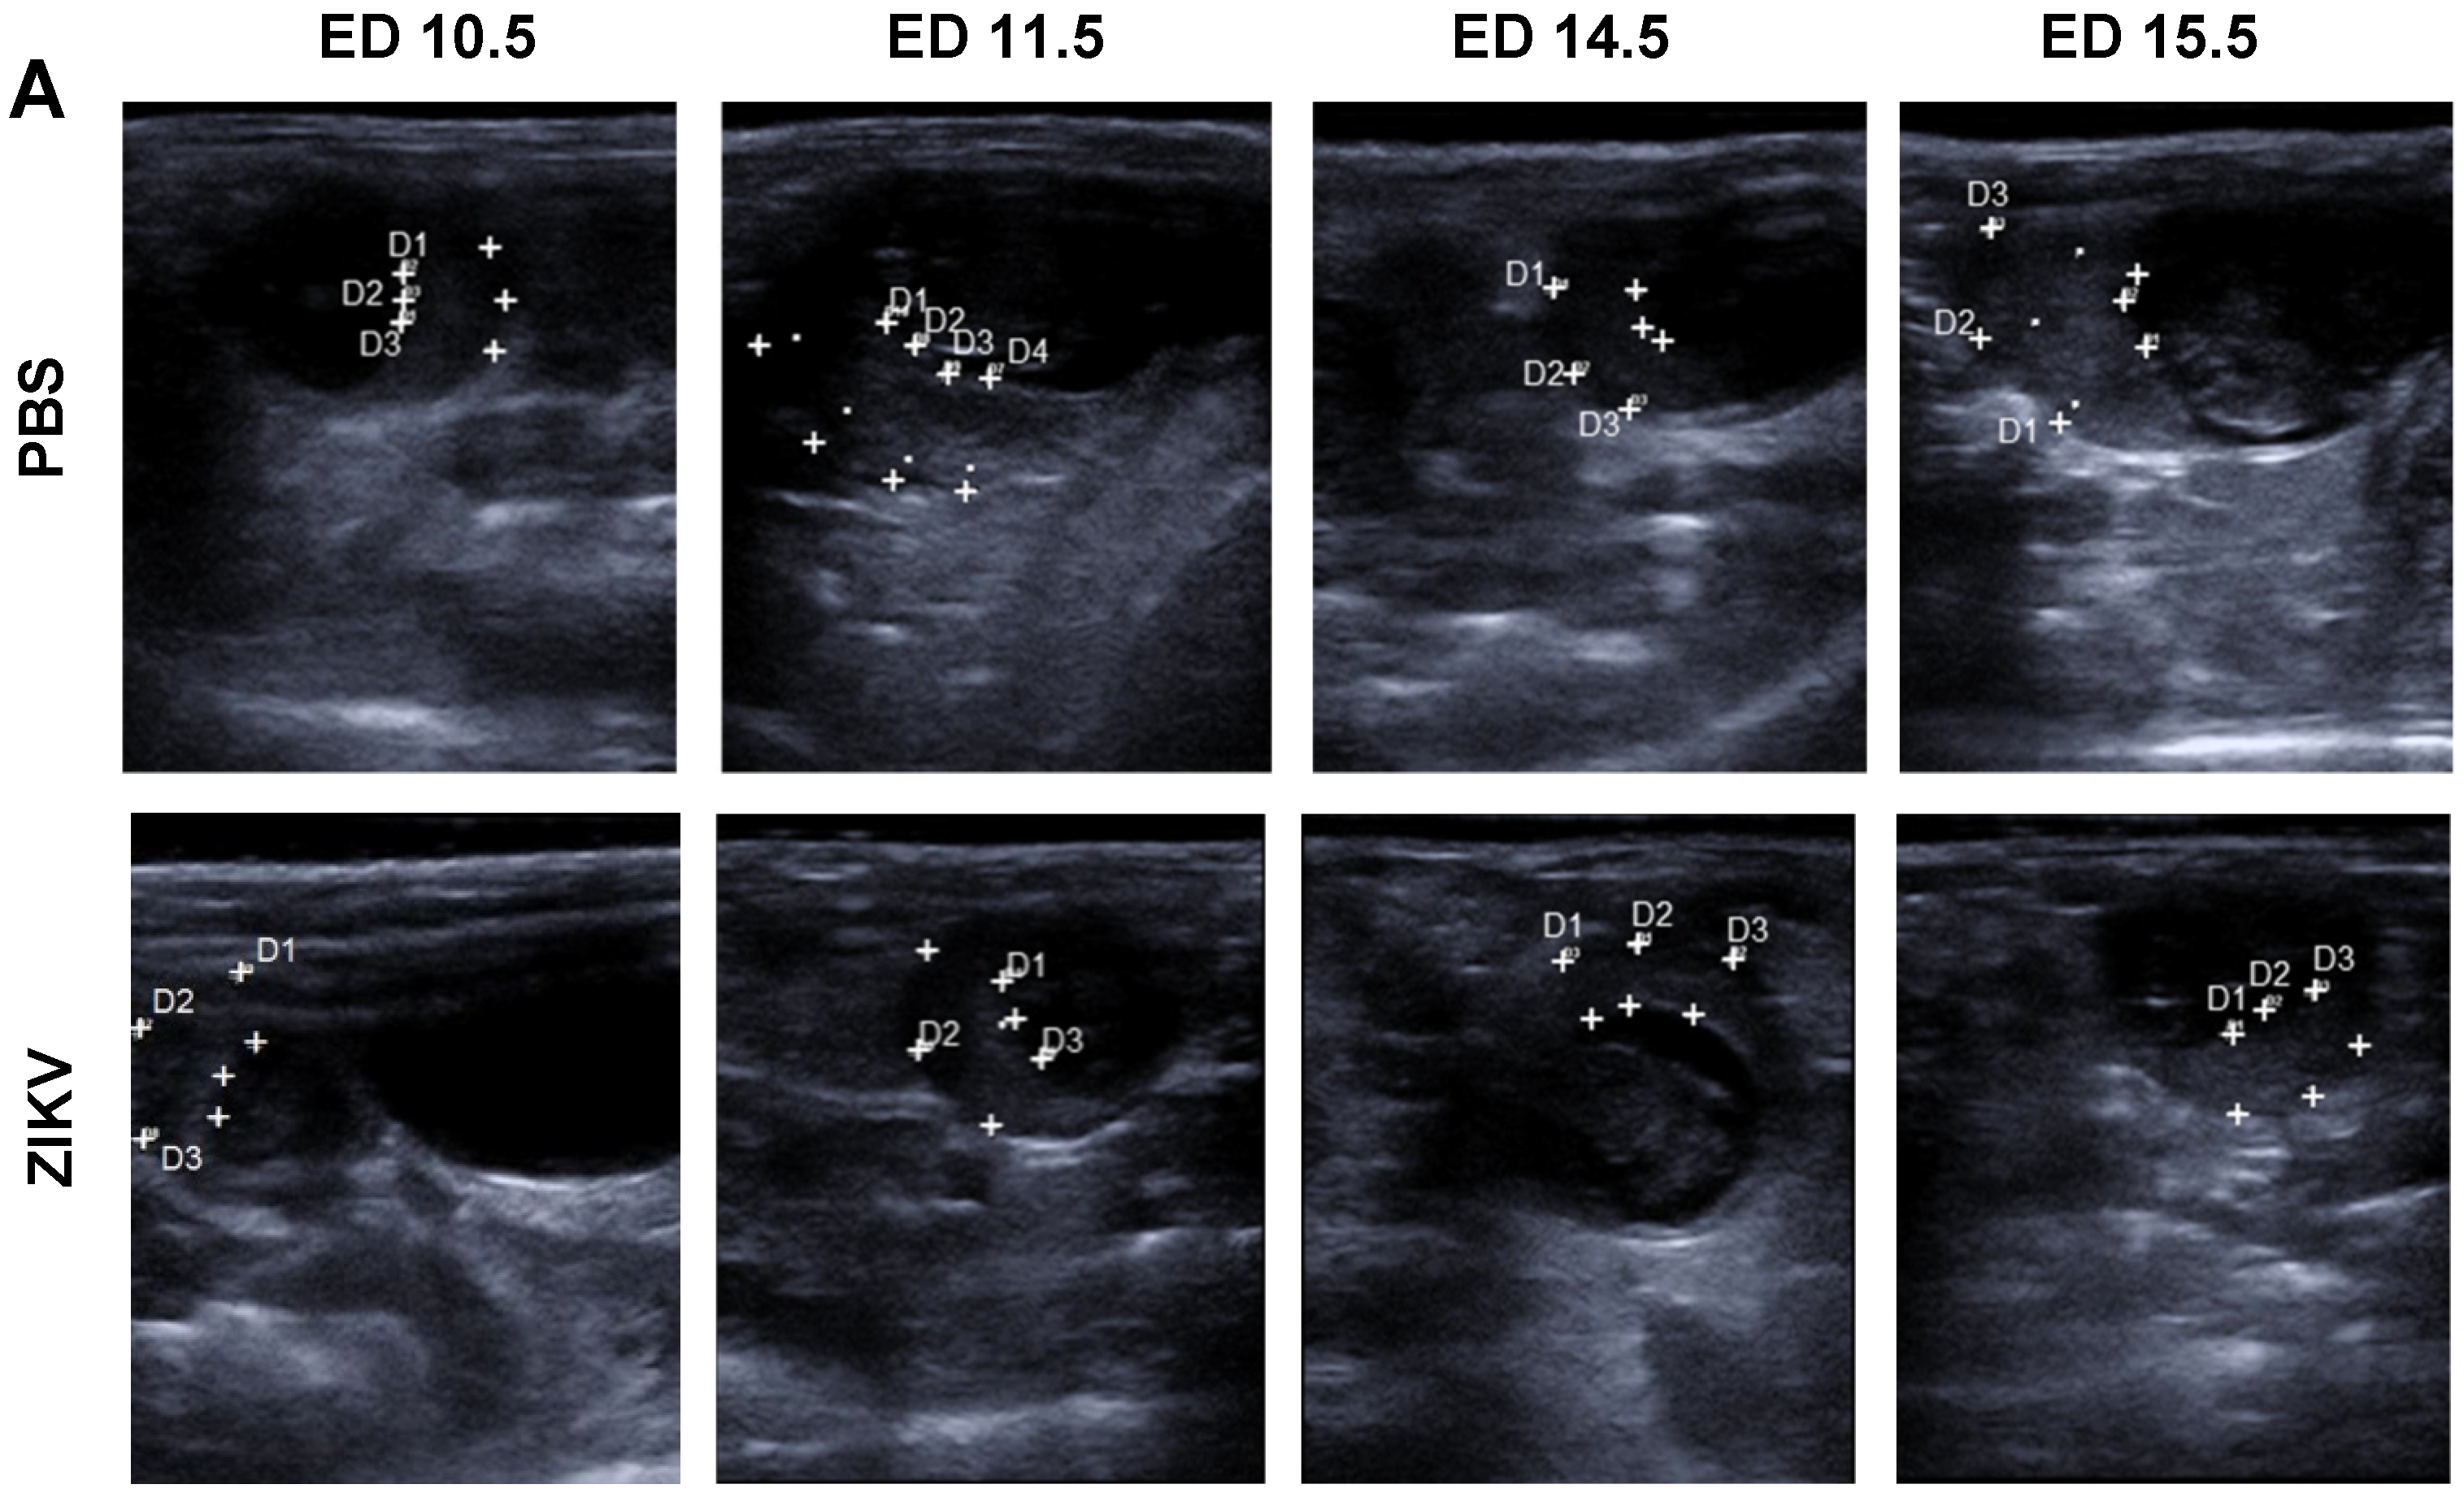

3.2. Evaluation of Uteroplacental Blood Flow Activity by Doppler Ultrasound

Direct Comparison between ED 13.5 and ED 16.5